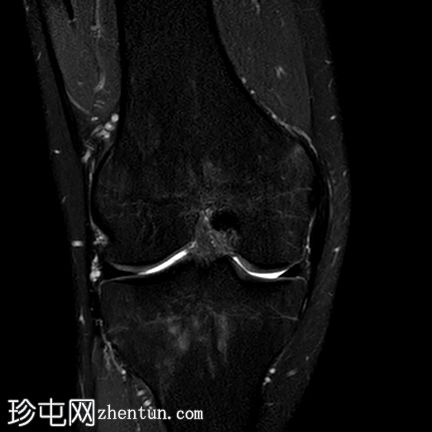

冠状位PD脂肪抑制序列

内侧半月板(体部)内缘呈波浪状,符合半月板皱褶。

延伸至关节面的线状高信号,符合水平撕裂。

前交叉韧带(ACL)近端高信号提示部分撕裂。

股骨内侧髁后方关节积液及骨髓水肿。

半月板皱褶在矢状位图像上表现为膝关节半月板内缘呈波浪状。它与半月板撕裂的发生率增加无关,不应与半月板撕裂混淆,尽管在本病例中两者同时存在。